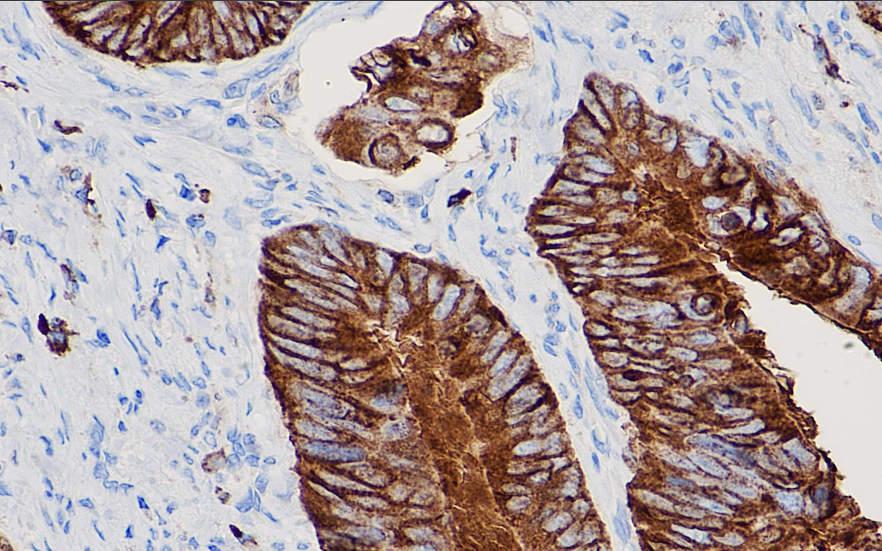

Positive control: Colorectal cancer

In the synthesis of prostaglandins, thromboxanes, and cyclooxygenides, cyclooxygenase-2 (COX-2) catalyzes the conversion of arachidonic acid into prostaglandin H2. The activity of COX-2 is inhibited by nonsteroidal anti-inflammatory drugs (NSAIDs), thereby reducing angiogenesis and tumor progression and promoting apoptosis. COX-2 is an inducible enzyme, and its expression can be upregulated by various factors such as endotoxins, infectious agents, and growth factors. Studies have shown that in head and neck squamous cell carcinoma, COX-2 overexpression increases microvascular density, and combined with VEGF expression, this indicates poor prognosis. Additionally, COX-2 overexpression in colorectal cancer, breast cancer, pancreatic cancer, and lung adenocarcinoma is also a marker of poor prognosis.

COX-2 antibody reagents can specifically bind to COX-2 molecular antigens. Immunohistochemistry kits containing COX-2 antibody reagents are suitable for the precise diagnosis of colon cancer, breast cancer, pancreatic cancer, lung adenocarcinoma, and squamous cell carcinoma of the head and neck.